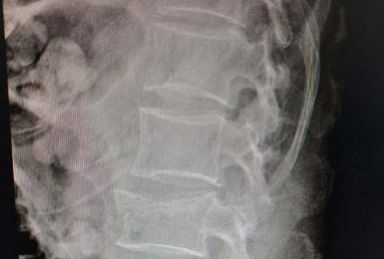

腰椎间盘突出可以治好吗?

腰椎间盘突出通常可以治好,但治疗效果因人而异,主要与病情严重程度、治疗方式选择以及患者自身康复情况有关。 腰椎间盘突出是一种常见的脊柱疾病,多数患者通过保守治疗能够有效缓解症状。保守治疗包括卧床休息、物理治疗、药物治疗等。卧床休息有助于减轻椎间盘压力,缓解...